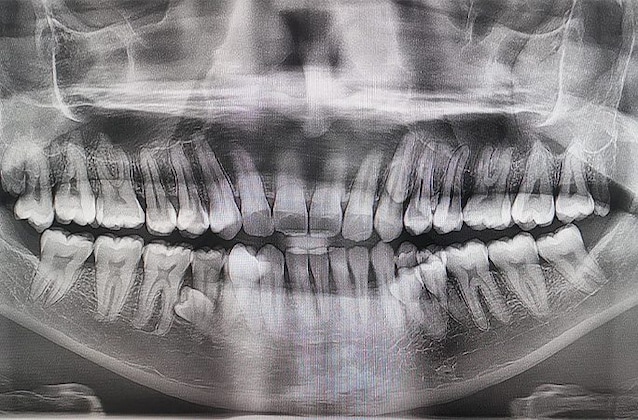

At that point, he and his relatives would realize they had a total 38 teeth: the subsequent dental panoramic would then confirm the presence of another 4 teeth ready to erupt. His story was verified in 2023, when two more dental visits confirmed the presence of 42 teeth total.

But how is that possible Prathab Muniandy does he have that many teeth? It is a defined condition “hyperdontia” which, as highlighted in this scientific study, is one of the most frequent dental anomalies, characterized by teeth in excess of the normal number (defined as “supernumerary teeth“) which can be present in both the maxillary and mandibular arches.